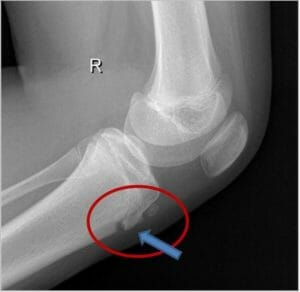

Las principales herramientas para confirmar el diagnóstico del Osgood-Schlatter se realizan mediante radiografías que pueden mostrar daño en la espina tibial, protuberancia ósea o si existe alguna alteración ósea u otras patologías de mayor importancia. Si no se refleja con mucha claridad, se puede realizar una ecografía o resonancia magnética.